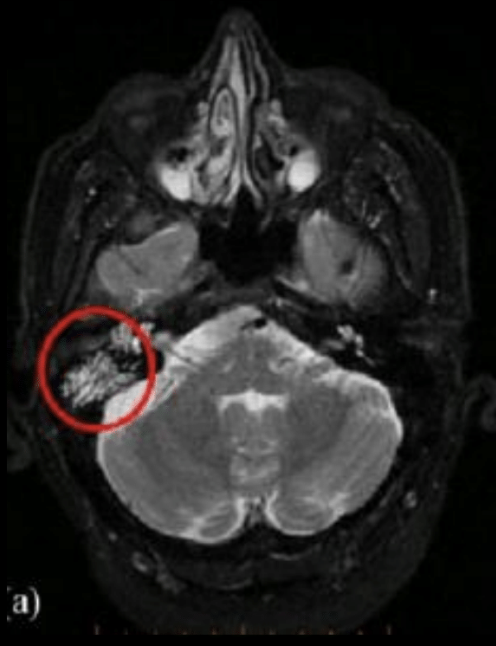

¿Para qué nos sirve la RM en otomastoiditis? ¿Qué ves en la imagen?

A

Para ver extensión intracraneal

Veo meningitis por la infección